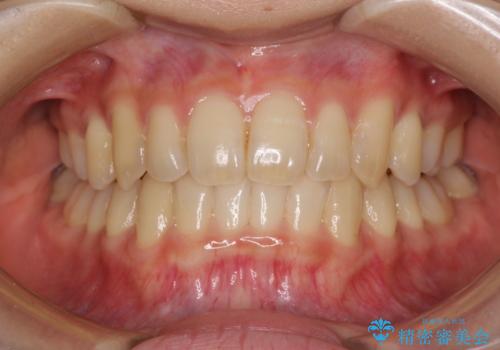

[インビザライン ライト] 短期間(3.5ヶ月)で終わるマウスピース矯正

![[インビザライン ライト] 短期間(3.5ヶ月)で終わるマウスピース矯正の症例 治療後](https://seimitsushinbi.jp/wp/wp-content/uploads/2020/02/2f36cdf472a802b537022ae239b8cb6b-500x350.jpg?v=1580813669)